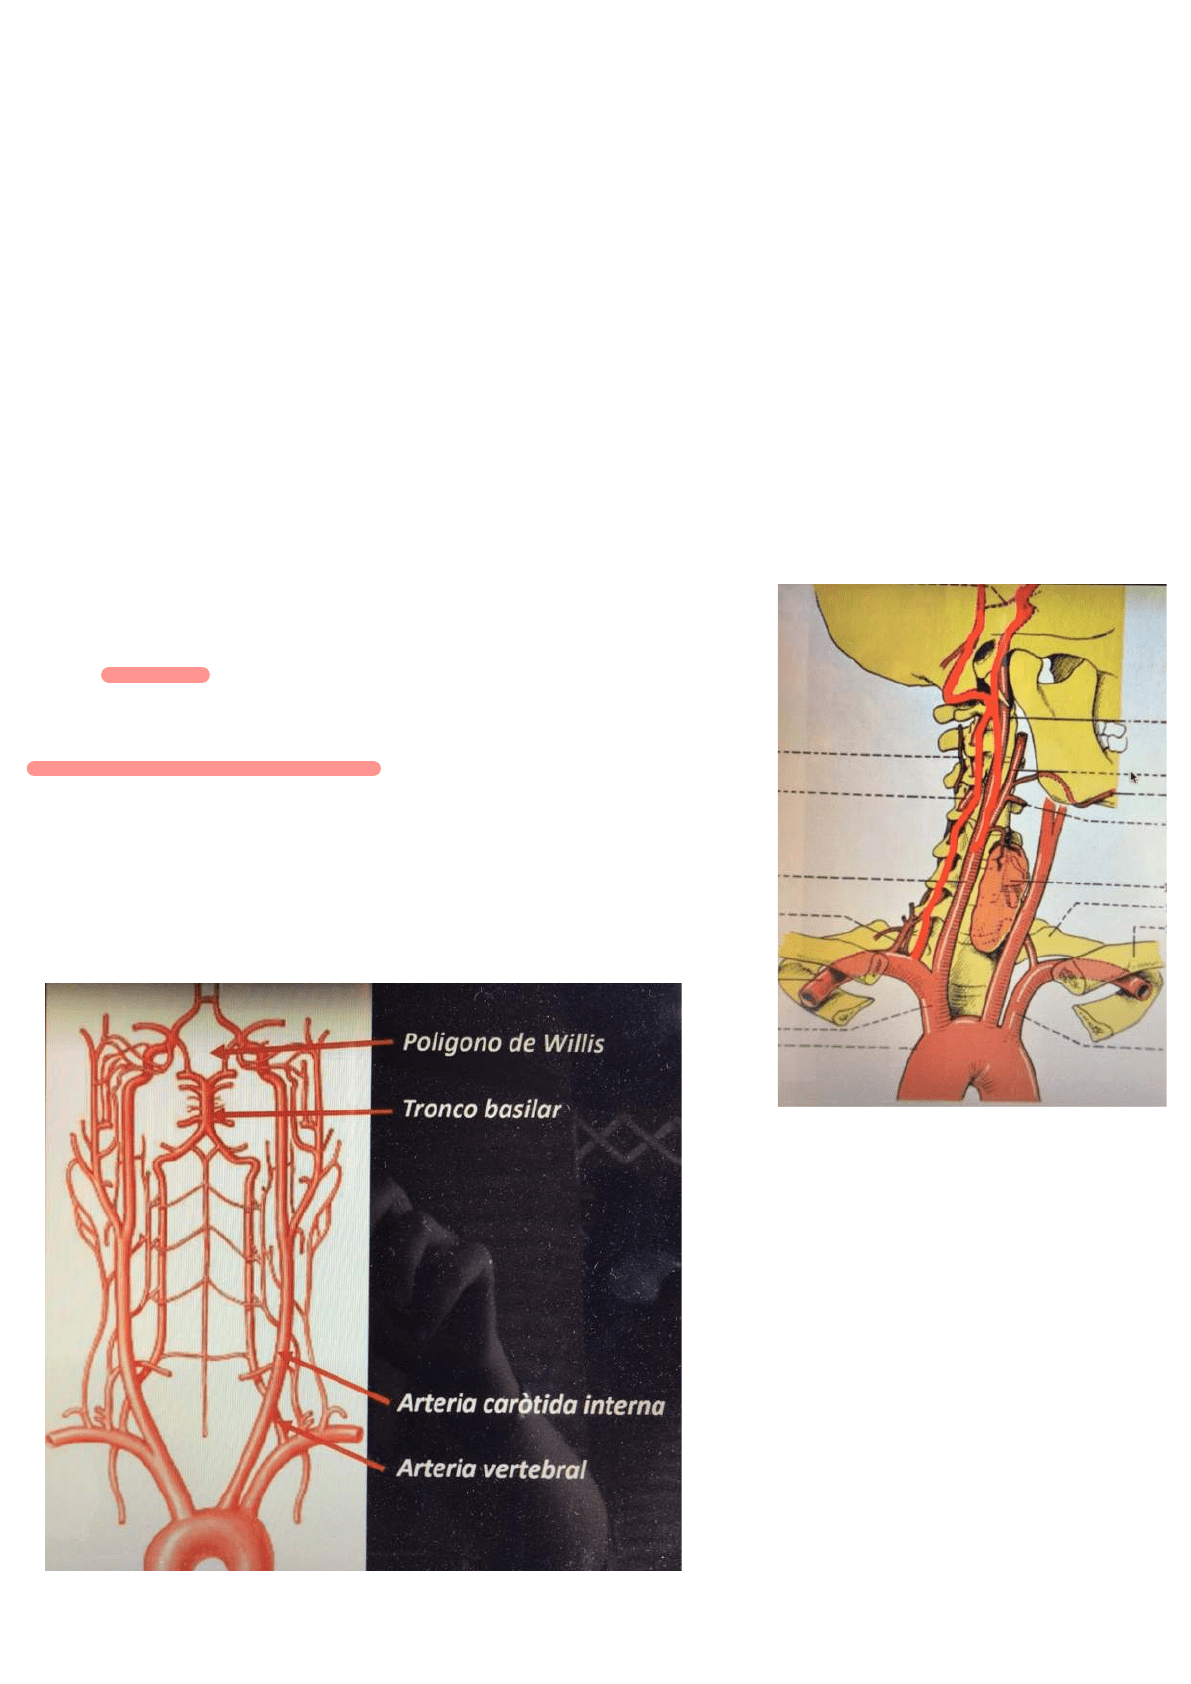

Irrigación del SNC

Irrigación arterial

Sistema de las arterias carótidas internas

Rama de la bifurcación de la arteria primitiva, division que se hace por un plano qué pasa por el borde superior del cartílago tiroides.

Atravesando el espacio maxilo-faringeo llega a través del orificio carotídeo ingresando al craneo.

Sistema de las arterias vertebrales

Son ramas de las arterias subclavias, que ascendiendo a través de los agujeros transversarios y a través del foramen magno/ agujero occipital ingresan al

cráneo.

Las arterias carótidas internas llegan por separado mientras que las arterias vertebrales se reúnen y

forman el tronco basilar.

Las dos fuentes están en contacto formado un circuito anastomotico situado en la base del cerebro:

Circuito arterioso del cerebro o polígono de Willis